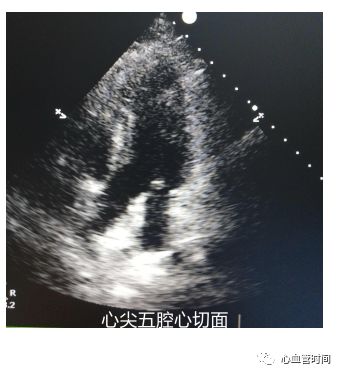

心尖五腔心切面

主要观察

主动脉瓣和

室壁。对于主动脉瓣重度狭窄患者,瓣口开放小,只有那么一个「小口」可以射血,血流还不一定是正着方向射出去,二维图像下往往不能测出最高速度。这时建议

结合彩色多普勒,显示出

血流的出口、

血流最亮的切面,尽量血流束与取样线平行,此时测量往往比较准确。

主要观察

主动脉瓣和

室壁。对于主动脉瓣重度狭窄患者,瓣口开放小,只有那么一个「小口」可以射血,血流还不一定是正着方向射出去,二维图像下往往不能测出最高速度。这时建议

结合彩色多普勒,显示出

血流的出口、

血流最亮的切面,尽量血流束与取样线平行,此时测量往往比较准确。